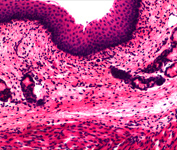

MD90数码成像装置可与任何标准的三目生物显微镜、体视显微镜、金相显微镜配合使用,拍摄数码显微图象,它具有传输速度快,色彩还原好,图象清晰,存储方便能优点,可以广泛的应用于工业品管、教学研究、材料分析,机器视觉等领域。MD90可以使你原本繁杂的工作变的轻松、有趣和高效。